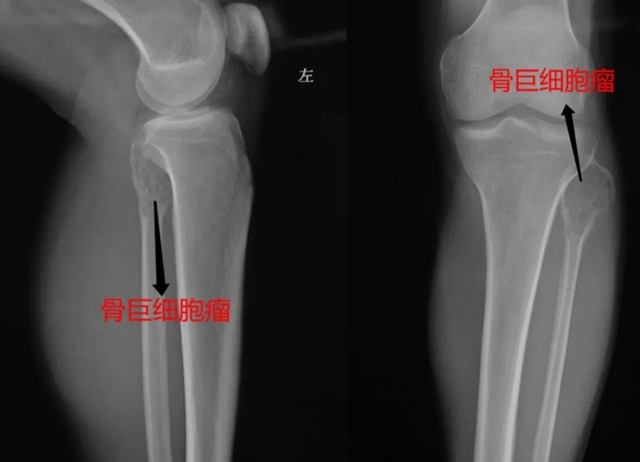

【罕见】泸州36岁男子小腿变粗长包,结果竟是……

【罕见】泸州36岁男子小腿变粗长包,结果竟是……西南医科大学附属中医医院 2022-08-07 17:39 发表于四川近日,36岁的孔先生因左小腿肿胀增粗、疼痛,可摸到包块,来到西南医科大学附属中医医院骨伤科脊柱·肿瘤一组就诊。经X、CT、...